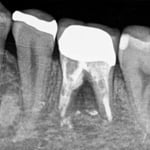

#穿孔修復(近心根の遠心壁)

大臼歯の近心根の遠心壁に大きな穿孔が生じていた症例です。体格の良い男性でした。CTによる読影でも、大きな透過像が確認されます。この症例は、チタンメッシュとスーパーボンドを用いて修復しました。

CTでは、頬側の骨が破壊されていないことがわかります。おそらく、治療できるギリギリの時期であったかもしれません。穿孔封鎖後、遠心根も近心根も清掃拡大し、バイオセラミックスにて根尖を封鎖し、グラスファイバーにて築造。上部構造は、メタルのクッション性、メタルマージンの補綴物によるフェルール(帯環)効果を考え、P.F.M.C.としました。

外科的な治療は、第一大臼歯であっても、患者さん個々の頬粘膜の開き具合などのよって可能な場合と不可能な場合もあり、歯牙の部位で可否を決定するべきでないと思っていますし、体格の良い男性でしたが、外科的な処置にはかなり臆病だと感じましたので、非外科的に治療ができてよかったと思っています。

術後、7年経過していますが、問題なく機能しています。

治療期間:約12ケ月(経過観察期間4ケ月を含む)

治療回数:12回(1回/月)

治療費:28万円(破折歯修復+根管治療+支台築造+補綴)※毎回の処置料は別途

リスク:再治療は困難なこと。(そもそも抜歯の症例)

※リスクはどのような治療にも必ずあること。